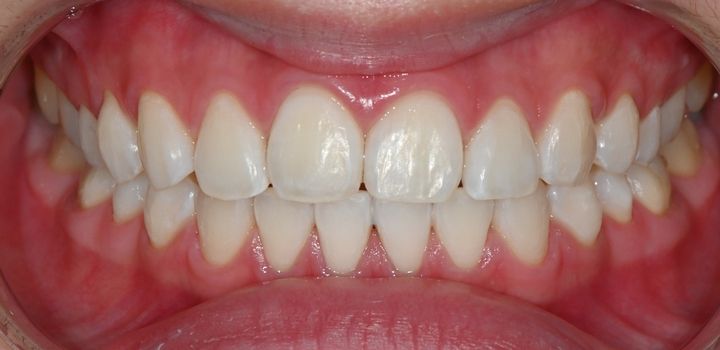

ハル歯科医院は、最先端のインプラント歯科治療に特化したクリニックです。代表のジョー・ハング院長は日本の神奈川歯科大学を卒業し、両国での歯科医師免許を保持。さらに、韓国で専門医資格を取得し、口腔外科など高度な手術経験も豊富です。すべての治療を院長自らが行う専任診療制を採用しており、流暢な日本語で対応可能。「デジタルインプラント」や「無削除ラミネート」などの最新のデジタル歯科治療を、日本の約半額で受けられます。仁川・金浦空港から乗り換えなしで行ける孔徳(コンドッ)駅すぐとアクセスも良好で、旅行者にも便利な立地となっています。

近所に住んでいる日本人でホワイトニングで訪れました。先生は日本語が流暢で歯科衛生士さんも少し日本語で対応していただけた為、安心感があります。一回のホワイトニングで歯が綺麗になったのでとても嬉しかったです。

今回ホワイトニングを1回受けました!

歯の色もすぐ白くなったし、凍みることもなかったです!

歯医者の先生が直接日本語で診療を見てくれました。

日本の歯科大学を卒業されたからか日本語がとてもお上手でした。